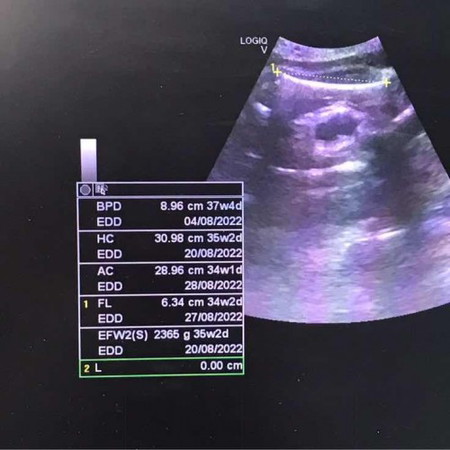

เพิ่งไปตรวจมาเมื่อวาน ข้อความในช่องสี่เหลี่ยม หมายถึงอะไรบ้างหรอคะ BPD HC AC FL EDD รุ้เเค่อย่างเดียวคือน้ำหนักในครรภ์ 2365 g หมอบอกว่าน้องน้ำหนักน้อยไปนิดเดียว ตอนนี้35วีค น้ำหนักลงเเม่หมดเลย ลงน้องน้อยมาก ตอนนี้เเม่น้ำหนักขึ้นมา 13 กิโลเเล้ว 🥲 เเม่บ้านไหนน้ำหนักลงตัวเองเยอะบ้านคะ ทำไงให้น้ำหนักลงน้องดี #ท้องเเรกค่ะ #ขอบคุณสำหรับคำตอบค่ะ #คุณแม่ๆช่วยแนะนำหน่อยค่ะ